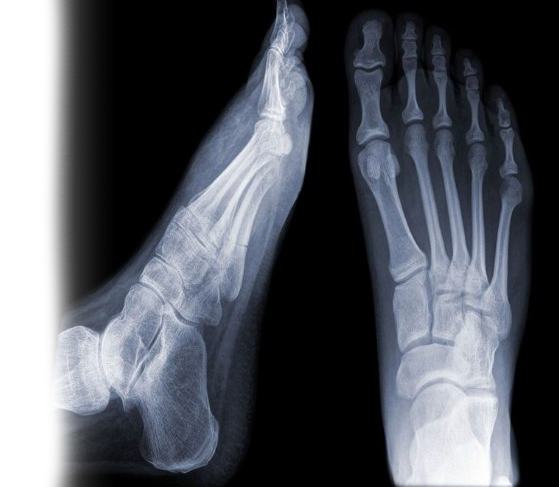

Рентгенография стопы

Рентгенография стопы – важный метод прицельного исследования, который позволяет оценить состояние стопы, а также отдельных областей стопы.

1. Рентгенография стоп с функциональной пробой – исследование, которое позволяет исключить патологию стопы ревматологического, костно-травматологического, дегенеративно-дистрофического генеза, а также оценить архитектонику (взаиморасположение костей) стопы.

2. Рентгенография пяточной кости - исследование позволяет оценить наличие костно-травматической, дегенеративно-дистрофической патологии пяточной кости.

3. Рентгенография плюсны и фаланг пальцев стопы – исследование позволяет исключить патологию стопы ревматологического, костно-травматологического, дегенеративно-дистрофического генеза.